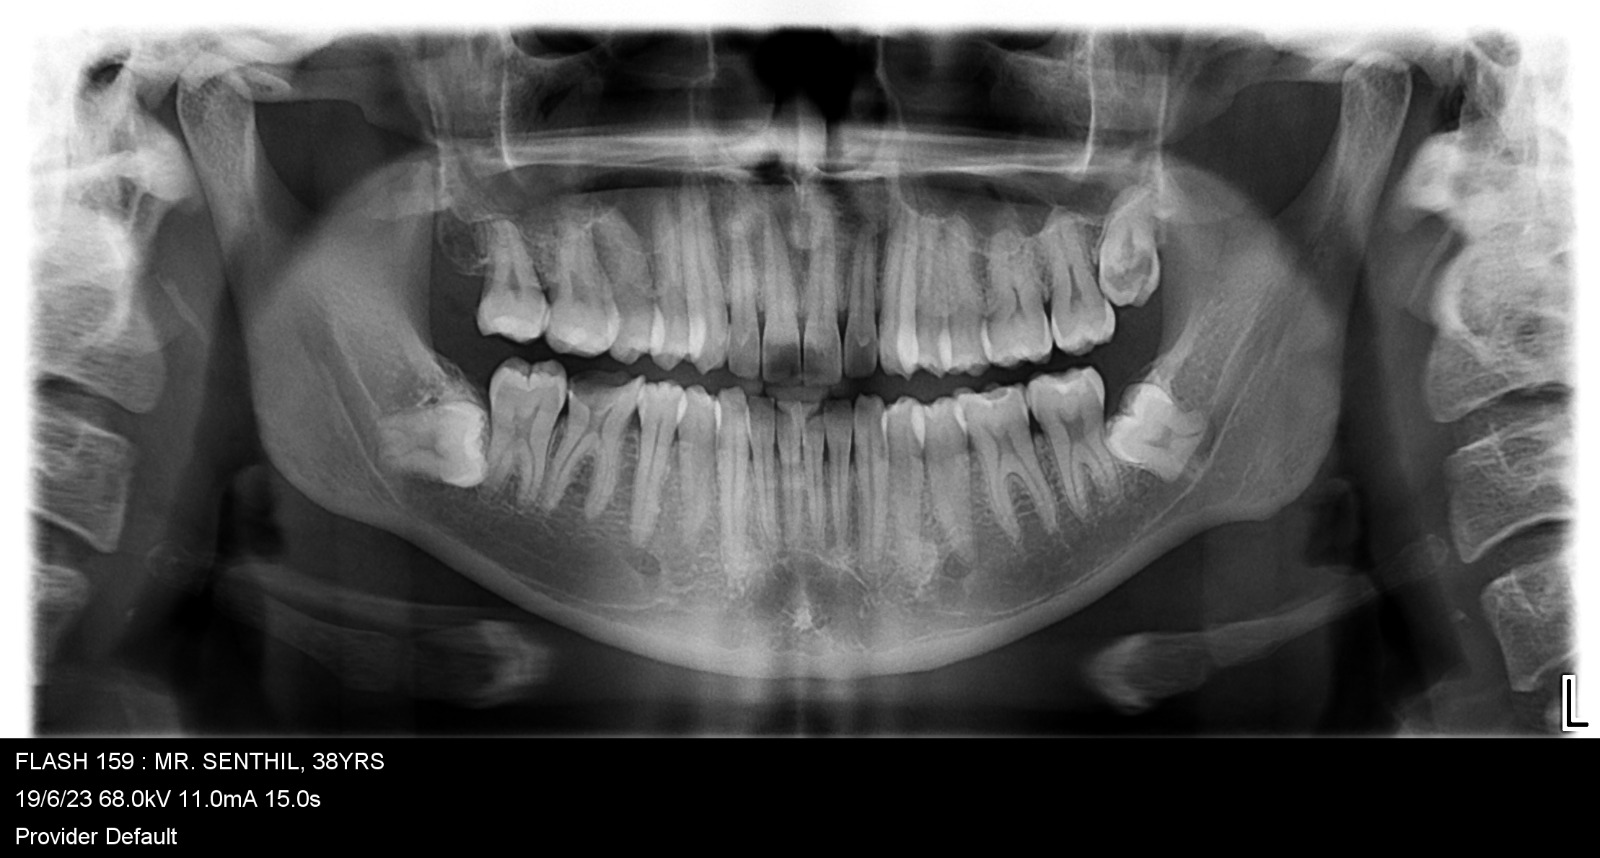

Images Of Dental Treatment Servcies Done At Our Hospital